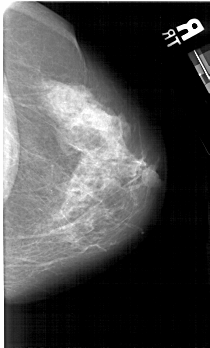

A_1631_1.RIGHT_MLO

RIGHT_MLO LINES 4861 PIXELS_PER_LINE 3286 BITS_PER_PIXEL 12 RESOLUTION 43.5 NON_OVERLAY